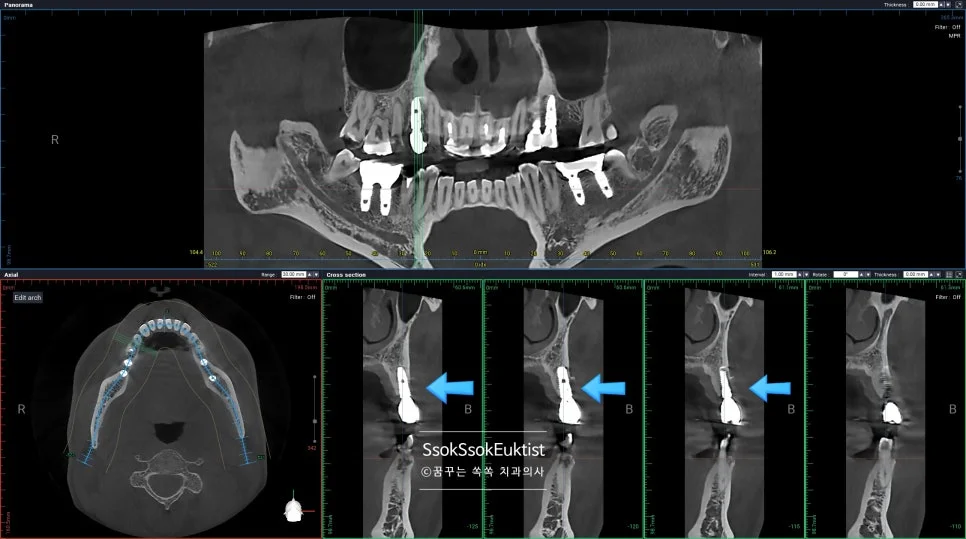

CBCT 단면 영상 — 임플란트를 감싸고 있어야 할 뼈가 다 녹아 없어진 모습

임플란트가 뼈와 유착에 성공은 하였다 하더라도 임플란트를 감싸고 있는 뼈가 부족하면 이렇게 점점 임플란트 주위염으로 뼈와 잇몸이 녹아내리게 되는데요.

이래서 임플란트는 가급적 깊게 그리고 입천장(혀) 쪽으로 위치하여 식립하여야 합니다.

이 임플란트는 점점 염증이 심해질 것이고 그나마 남아 있는 잇몸까지 녹게 되면 이후의 치료가 너무 어려워지기에 임플란트를 제거한 후 재식립을 시도합니다.